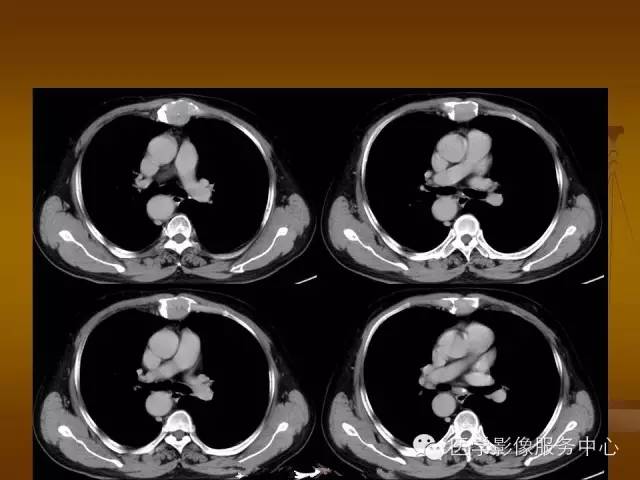

胸骨浆细胞骨髓瘤1例CT影像表现

特征性穿凿状、鼠咬状及蜂窝状骨质破坏,边缘清楚,骨质疏松,病理性骨折及软组织肿块等表现,骨质硬化及骨膜反应少见。

骨质破坏区完全为软组织取代,骨质膨胀,边界清楚,常突破骨皮质形成软组织肿块。

增强扫描可见病灶轻中度强化,一般于静脉期达峰值。